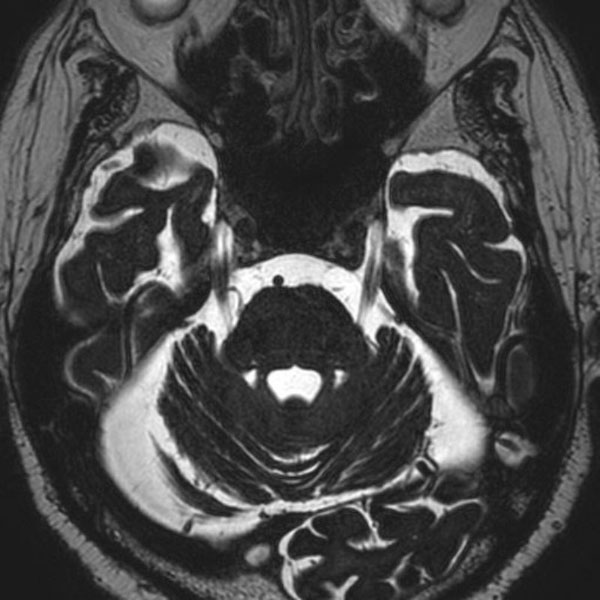

手術前

(MR1)